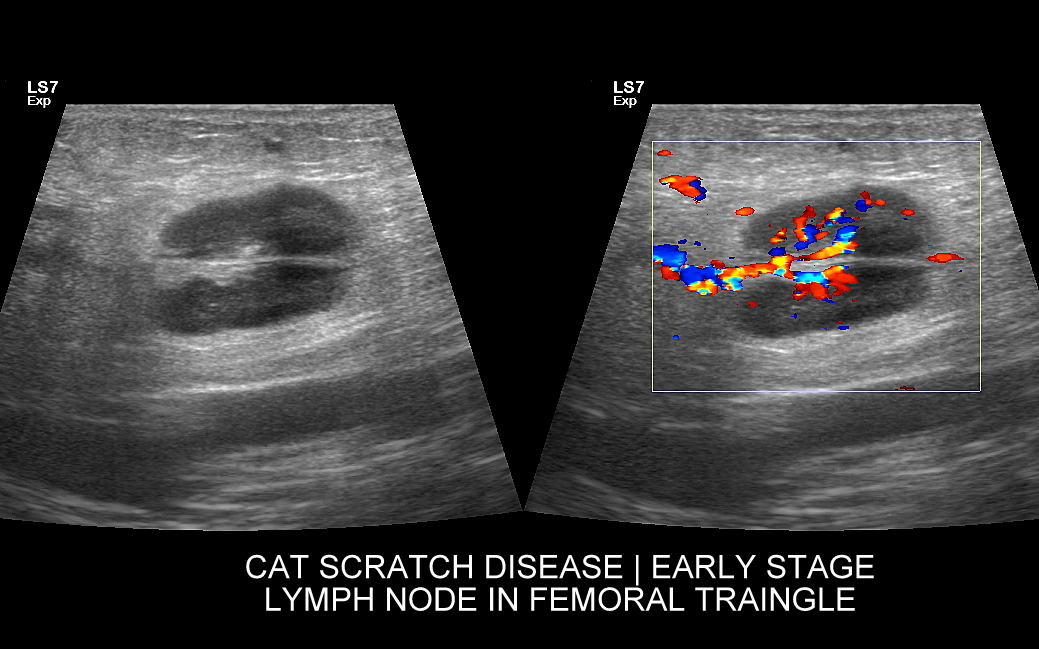

Węzły limfatyczne pachwinowe najczęściej ulegają powiększeniu w przebiegu chorób zapalnych i zakaźnych lokalizujących się w kończynach dolnych. Przykładami są takie schorzenia infekcyjne jak róża, zapalenie tkanki podskórnej (cellulitis), ropnie, czy w cale nierzadka choroba kociego pazura (ang. cat scratch disease) wywoływana przez bakterię Bartonella hensellae, której to źródłem są koty i żyjące na nich pchły. Pachwinowe węzły chłonne powiększać się mogą również w trakcie chorób zapalnych lokalizujących się w okolicy krocza, moszny oraz układu rozrodczego. Limfadenopatię pachwinową spotyka się w przebiegu chorób onkologicznych.

Badanie USG jest podstawową metodą obrazowania węzłów chłonnych. W jego trakcie ocenia się nie tylko wielkość węzłów, lecz także ich kształt, proporcje wymiarów, morfologię, czyli wygląd zewnętrzny oraz strukturę wewnętrzną, ich unaczynienie, spoistość, a także tkanki otoczające. W trakcie interpretacji badania pod uwagę bierze się również zbierany od pacjenta wywiad chorobowy oraz wyniki innych badań obrazowych i laboratoryjnych takich jak morfologia, OB, CRP, żelazo, ferrytyna, TIBC, innych parametrów infekcyjnych, a także onkologicznych. Ultrasonografia węzłów chłonnych jest procedurą bezpieczną i dokładną. W Pracowni dr Szczepańskiego węzły chłonne oceniane są nowoczesną metodą MPUS (multiparametryczne badanie USG), w szczególności z zastosowaniem trybów mikrounaczynienia i elastografii.